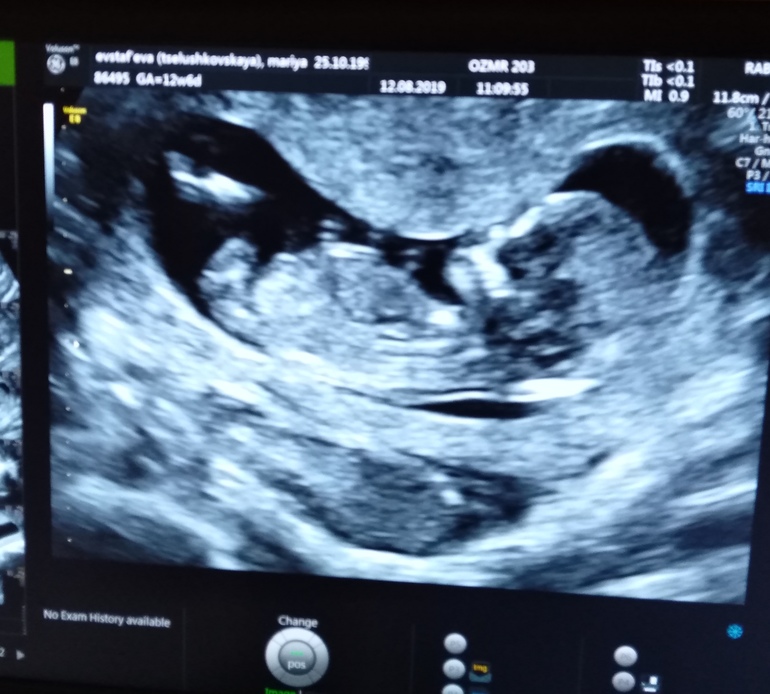

Всем привет!)) дождалась наконец-то я первого скрининга. Врач была более чем молчаливой , такое ощущение, что на меня внимания не обращала))) говорила все показатели ребёночка, всё с ним в порядке, соответствует сроку. Про пол молчала. Я спросила, она сказала, что только предпологать может, но потом снова начала мед сестре говорить замеры. Но сфоткать дала. Как кажется вам девочки??Женя

Мне кажется мальчик, но это только догадки)) Если то, что я вижу между ног это половой бугорок и он поднят вверх, у девочек он прямой. Вроде на Вашем фото он приподнят) Хотя если под другим углом смотреть он прямой...в общем не пойму 🙈

А покажите мне где этот самый половой бугорок?? Я ничего не вижу..

Может я ошибаюсь и это не он, в узи я дилетант 😁 Но я на эту часть смотрела, у меня ребенок лежал в таком же положении и узист показала в этом месте половой бугорок)

Я спрашивала у узистки она сказала это ноги! это бедро 😀а дальше продолжение ноги они согнуты

Мне предположили девочку, она лежала в таком же положении и между ног такой же яркий бугорок как у Вас косточка)) Только бугорок был прямой, жаль у Вас не видно его, так бы погадали)))

Я думала если мальчик, то бугорок должен торчать ну или хотя бы видеться между ножек))) до 16 недель похожу и пойду ещё раз куда нибудь схожу 😅

Половой бугорок есть у всех детей, на сроке 12 недель у девочек он прямой, у мальчиков приподнят вверх) Я ходила на узи в 14 недель и мне там тоже подтвердили девочку, думаю скоро должны и у Вас увидеть)))